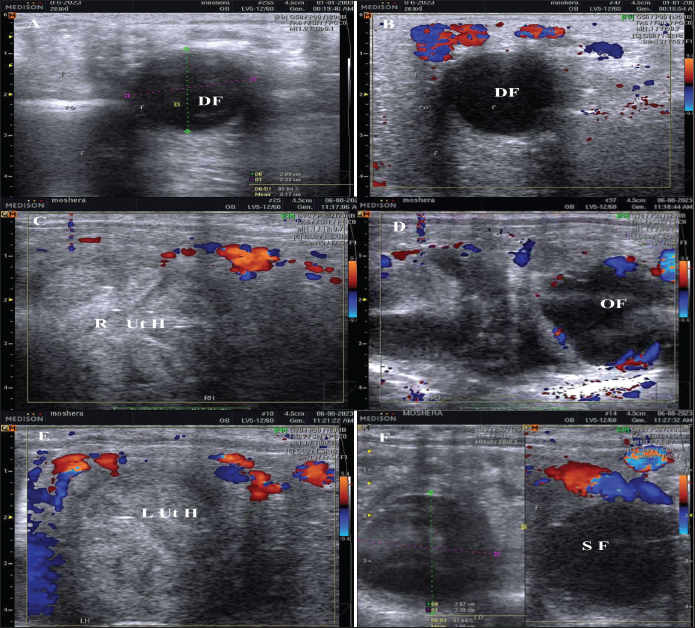

The ultrasound-Doppler scanner equipped with a12.0 MHz linear-array trans-rectal transducer (SonovetR3, Medison, Samsung, South Korea) was used for the examination of follicles or corpora lutae and uterus with their hemodynamics. Ovarian dominant and subordinate follicles and the corpus luteum (CL) were monitored using the ordinary greyscale and color Doppler modes (Fig. 1).

Fig. 1. The dominant follicle (DF) of 23.3 mm in diameter in grey scale (A), and color Doppler (B). The right uterine horn (R Ut H) showing the cart wheel characteristic of estrus and the uterine blood flow in color Doppler (C) and the characteristic polygonal shape of the preovulatory follicle (OV) in color Doppler (D), the left uterine horn (L Ut H) in the same mare and the same day in color Doppler, the subordinate follicle (SF) in grey scale and color Doppler (F).

The difference in the diameter, shape, and blood flow vascularization of the dominant, pre-ovulatory, and subordinate follicles are presented in Figure 1. The characteristic uterine edema during estrus and the uterine Doppler vascularization is presented in Figure 1.